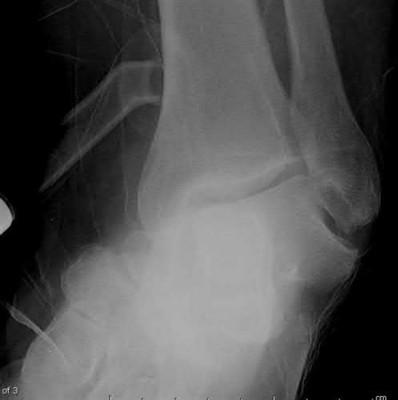

Figures A through C are AP, oblique, and lateral radiographic views of a right ankle demonstrating displaced fractures of the lateral and posterior malleoli. Figure D is an axial CT scan of the right ankle following closed reduction and splint application.

Figures A and B are the Lateral and AP radiographs of a displaced talar neck fracture with tibiotalar dislocation. Figures C and D are the post-reduction sagittal foot CT cuts that reveal a displaced talar neck fracture with medial

comminution.